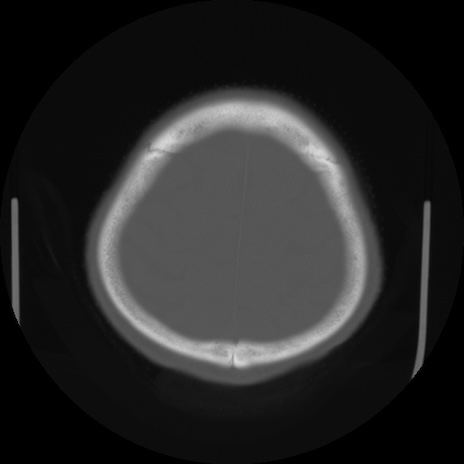

【頭部】症例5 CT(横断像)

【症例】80歳代 男性

【主訴】頭部打撲

【現病歴】外出先で椅子から立ち上がる際に、つまづいて後方へ転倒し受傷。転倒時に意識はあった。

【既往歴】高血圧、不整脈、アルツハイマー病

【身体所見】BP 217/71、HR 96、JCS1-1、 難聴あり、顔色良好、右後頭部に擦過創あり。神経学的異常なし。

症例5の画像所見と診断は?